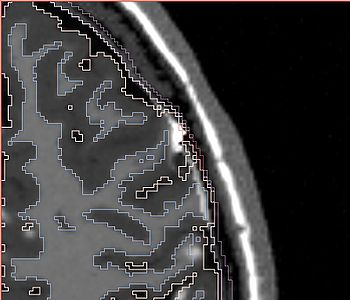

NOTE: red outlines the boundary of the label corresponding to the initial tumor seed!

All the following experiments are based on the "thin dura" input labels, and the tumor seed image shown on the right. The tumor label is shown in green color. Note that the tumor is touching the gray matter label.

The seed image can be downloaded File:Seed3.nrrd

The following screenshots capture the same axial slice (#119) of the following images in order: (1) image containing the tumor probabilities, and (2) the simulated Gad enhanced image, both overlayed with the warped tumor/brain tissues labels.

Poisson ratio 0.4

Poisson ratio 0.2